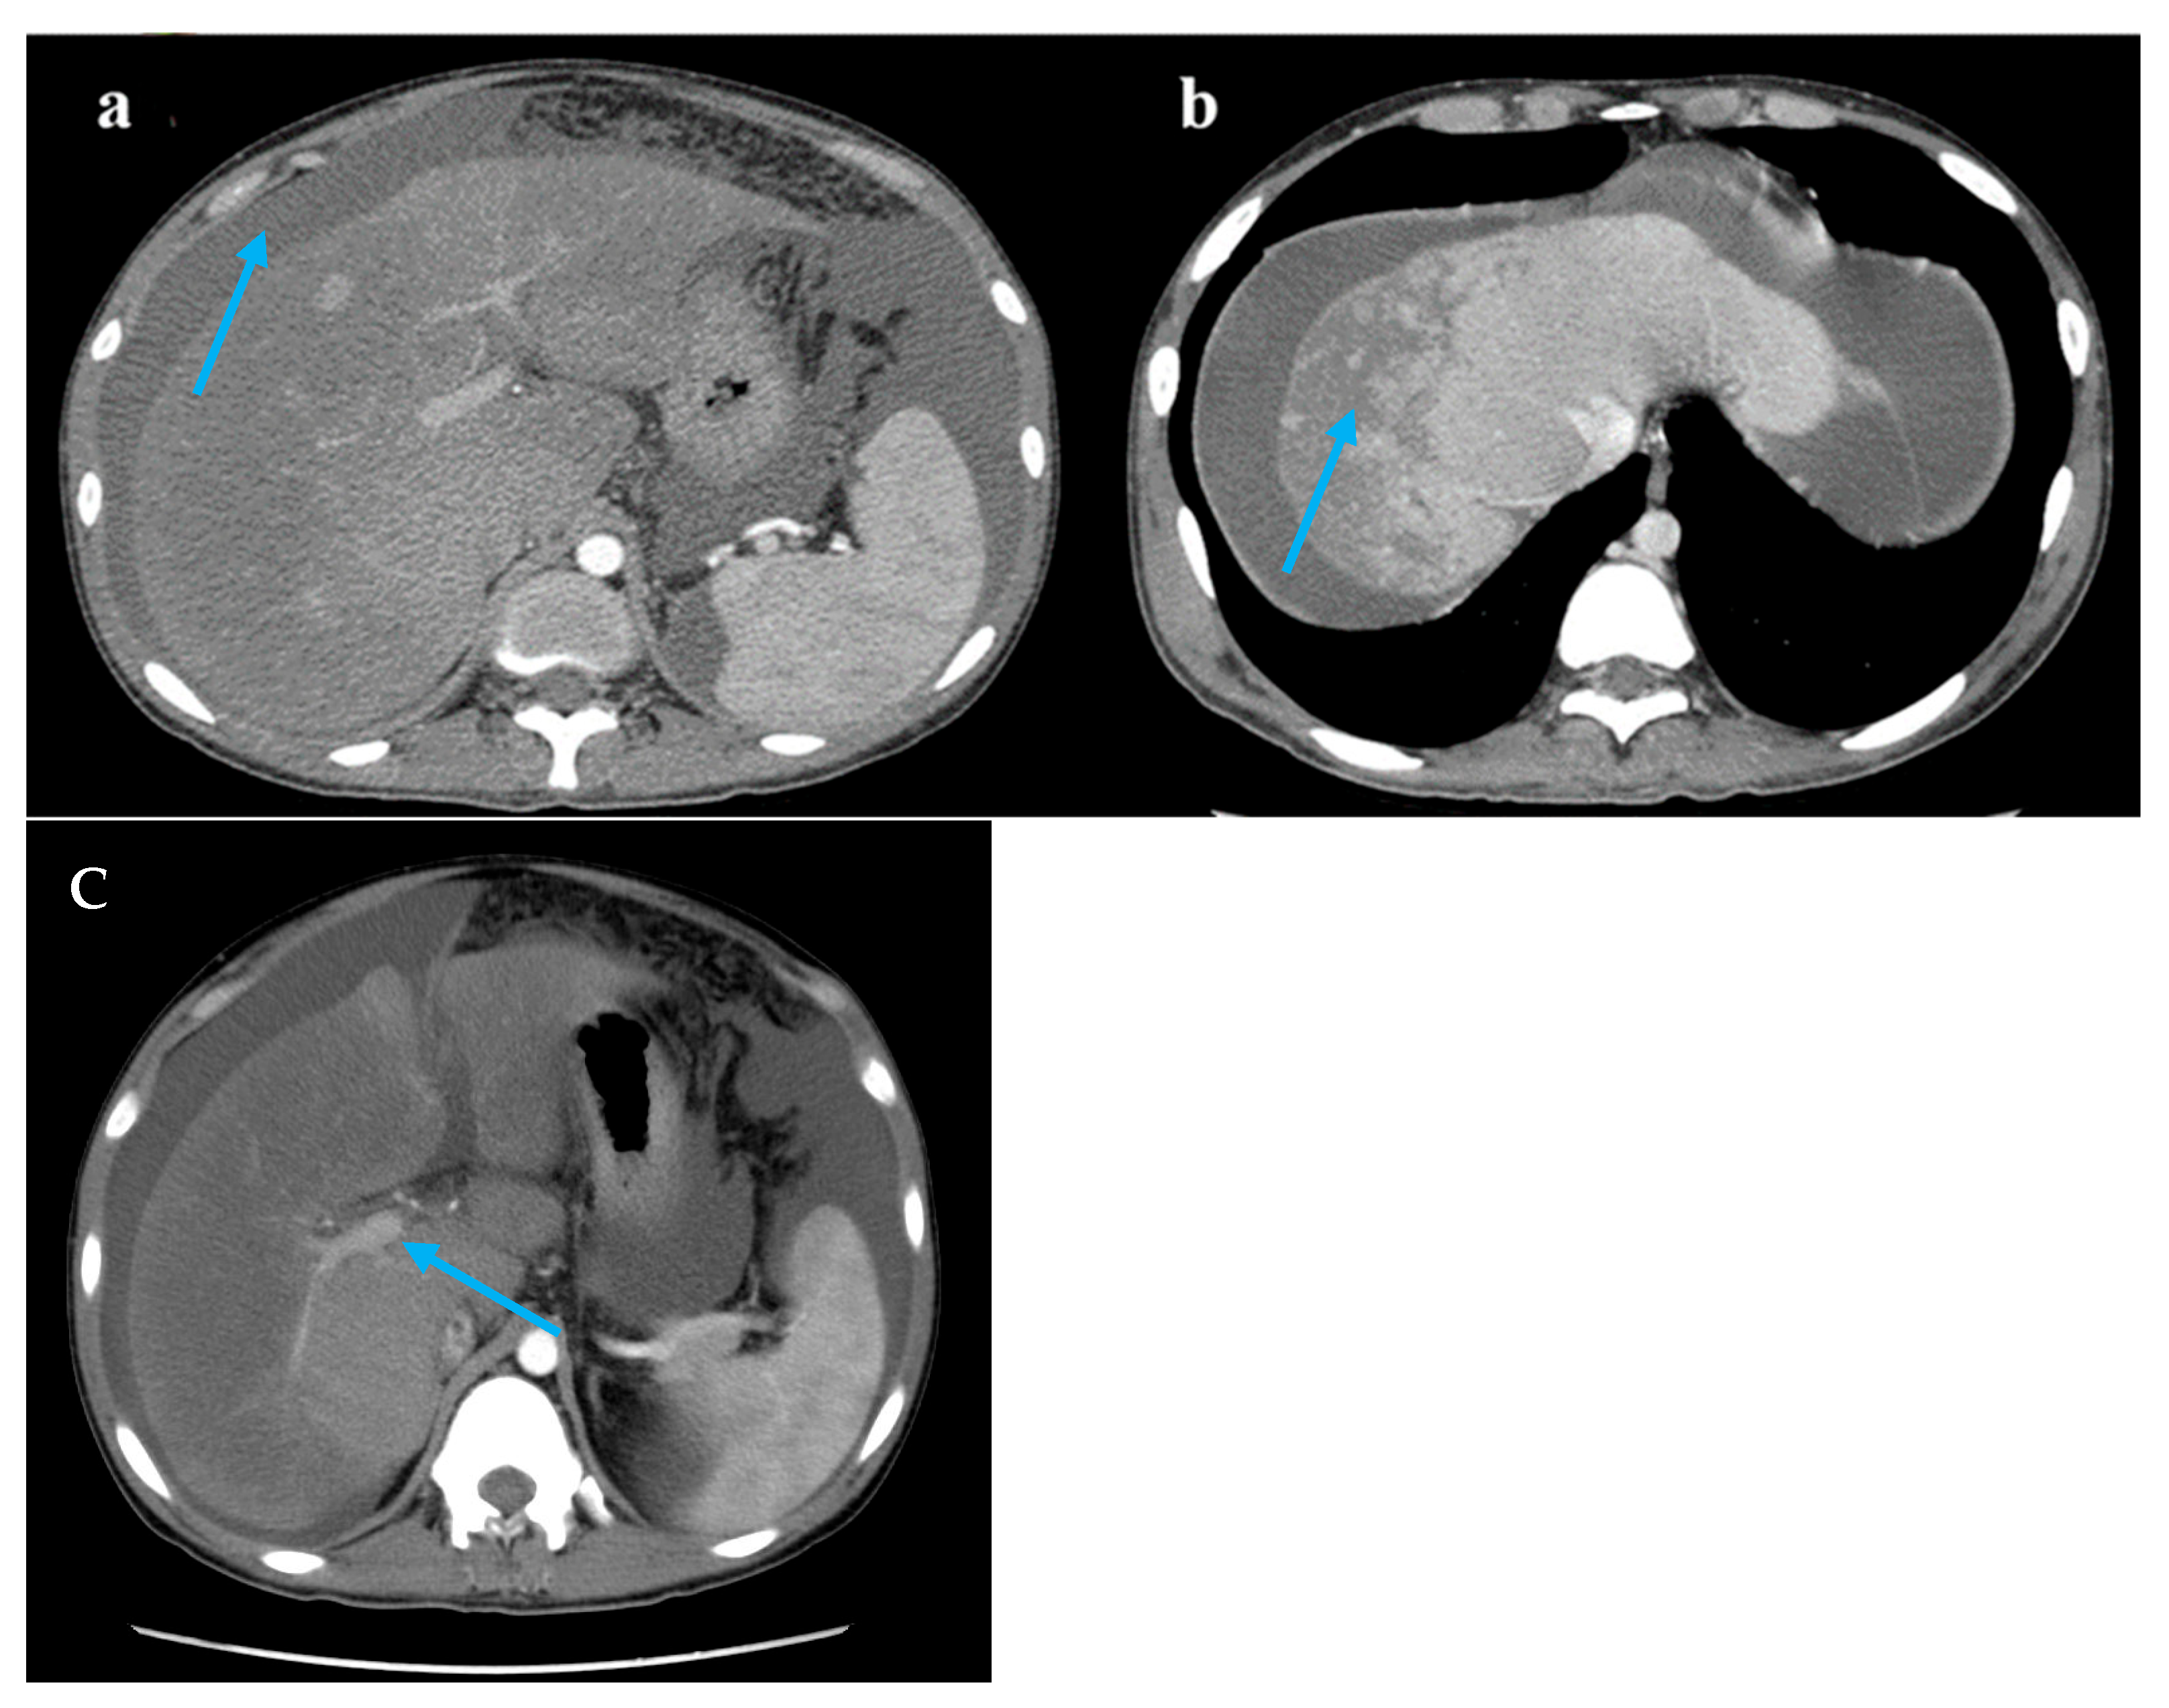

Figure 1.

Computed tomography images. Legend: (a) A large accumulation of fluid in the abdomen and pelvis (blue arrow). (b) The liver lobes exhibit balanced proportions. Diffuse, non-uniform reduction in liver density is observed. Areas of reduced density show low contrast enhancement on contrast-enhanced scans. Multiple nodules are visible within the low-density regions (blue arrow). (c) The hepatic veins are thin, and the portal vein is less full (blue arrow).